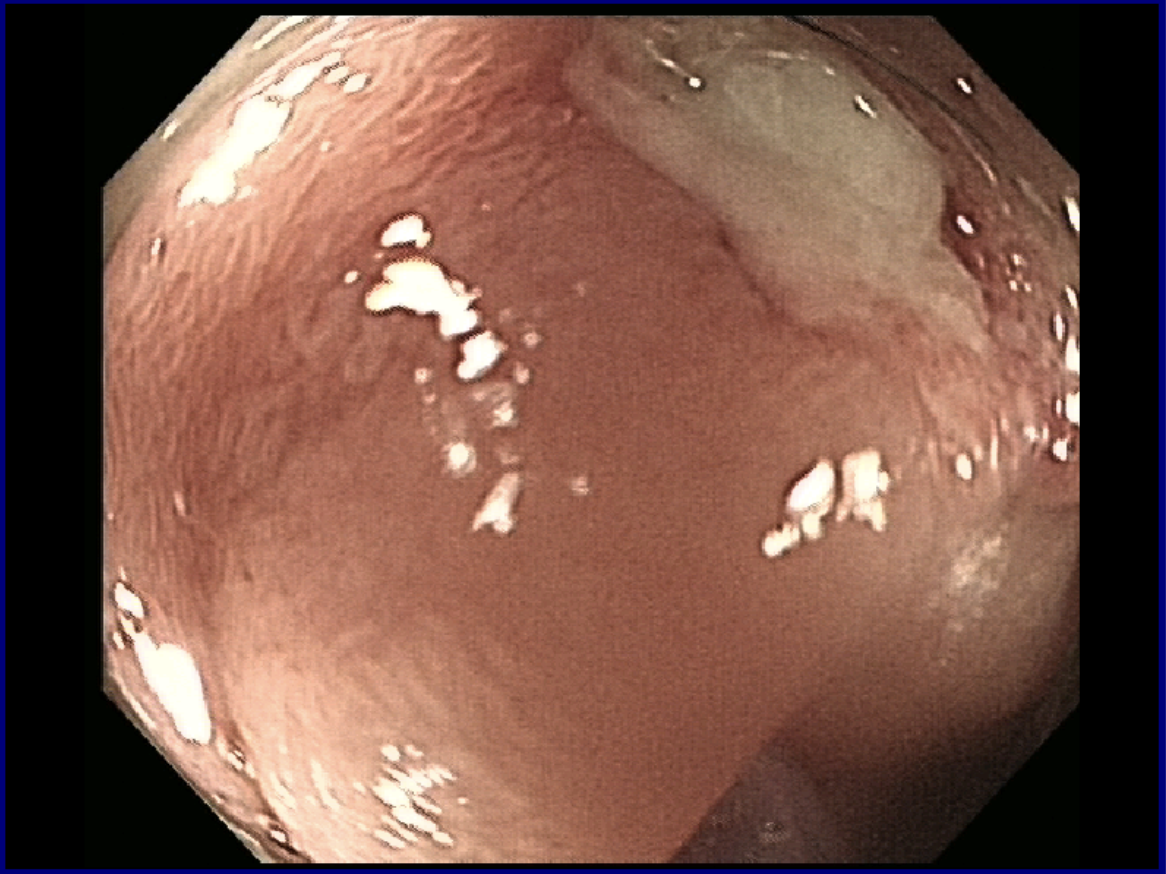

嵌顿的羊骨已造成患者十二指肠深溃疡。

异物被顺利取出。